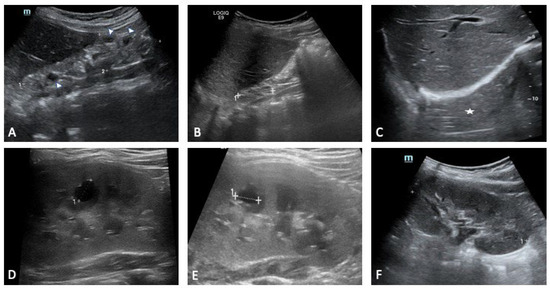

Background: The 17q12 recurrent deletion syndrome is a genomic disorder encompassing a 1.4 to 1.5 Mb region that includes the HNF1B gene, and it manifests with remarkable phenotypic variability. Renal anomalies, endocrine and metabolic disturbances, and neurodevelopmental or psychiatric disorders are recurrent features, [...] Read more.

Background: The 17q12 recurrent deletion syndrome is a genomic disorder encompassing a 1.4 to 1.5 Mb region that includes the HNF1B gene, and it manifests with remarkable phenotypic variability. Renal anomalies, endocrine and metabolic disturbances, and neurodevelopmental or psychiatric disorders are recurrent features, although penetrance and severity differ widely between patients. Methods: We reviewed the literature on the molecular basis, clinical presentation, diagnostic approaches, and management of 17q12 deletion syndrome, and we illustrate the variability of this condition through two contrasting paediatric cases. Results: The cases concern three siblings harbouring the same familial deletion, who nevertheless exhibited striking intrafamilial variability, ranging from renal and neurodevelopmental features to multisystemic involvement. These cases exemplify both extremes of the syndrome and highlight the challenges of clinical prognostication. Conclusions: The review and cases emphasise the importance of early genetic testing in paediatric renal anomalies, the necessity of multidisciplinary surveillance even in asymptomatic individuals, and the relevance of 17q12 deletion as a model of variable expressivity in genomic medicine. Full article

Show Figures

Figure 1